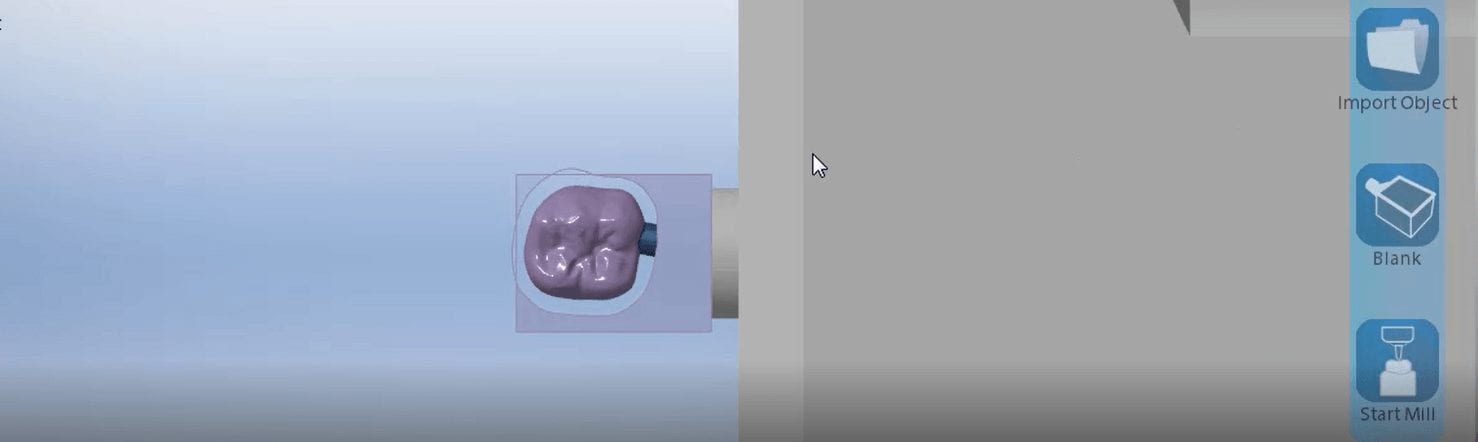

This article is for advanced users, where we detail a quick and easy scan, design, and mill. While the patient is anesthetized, the preop images are scanned. Excess data is […]